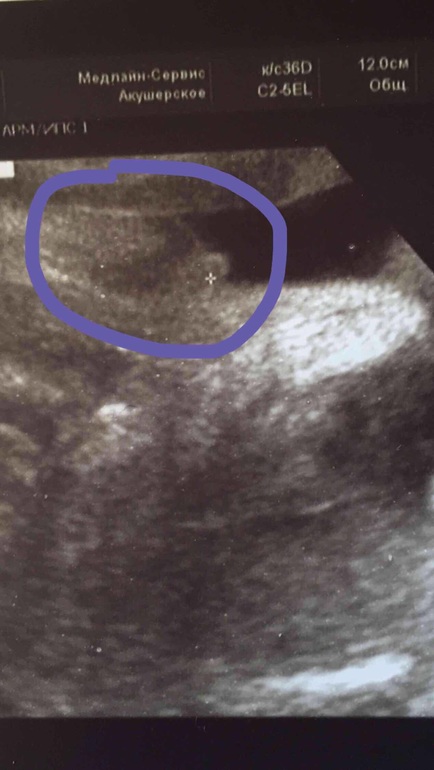

УЗИ в 30 недель

ДругоеСегодня на УЗИ сказали похоже девочка. А вы что скажете? Разве похоже на девочку? Крестиком отметил узист то самое.

это наш писюн мальчуковый на 22 неделе. А у вас...конечно я ж не спец...клитор может быть такой большой на 30 неделе? Может вполне и пацан, просто не под тем углом)) сходите отдельно на УЗИ , пол посмотрите!!!))И пишите сдесь, оч интересно!!!)

я девочку вижу...у меня с сыном в 14 недель отросточек побольше был